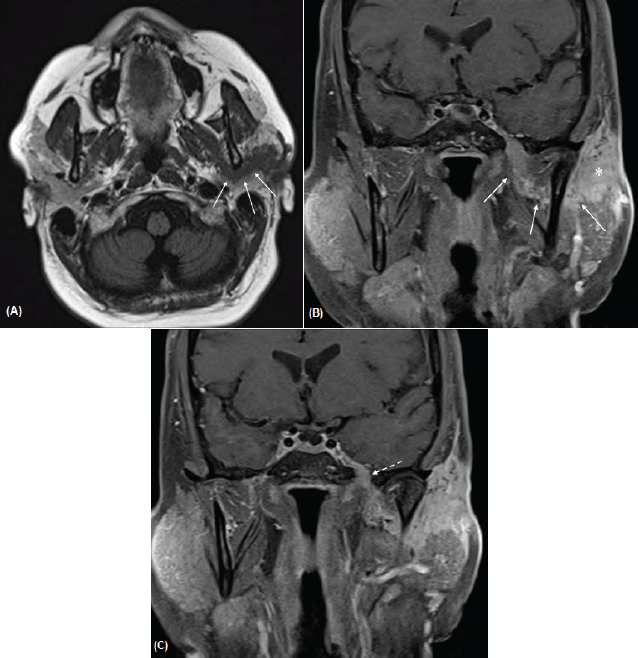

A magnetic resonance imaging (MRI) examination was performed (Figure 2). This demonstrated a lobulated mass measuring 2.0 × 2.2 cm within the superficial lobe of the left parotid gland with extension to the overlying capsule and thickening of the overlying skin. Thick curvilinear enhancing tissue was noted to be extending from the parotid mass around the posterior ramus of the mandible and joining with the V3 trunk in the left masticator space that corresponds to the track of the auriculotemporal nerve. Contiguous thickening and enhancement along V3 superiorly through a widened foramen ovale was noted. There was also slight thickening in the adjacent inferior aspect of the left cavernous sinus. These findings were compatible with perineural tumour spread along the left auriculotemporal nerve with contiguous extension to involve the left V3.

Figure 2 A–C. Axial T1-weighted image (A) and post-contrast coronal T1-weighted images with fat saturation (B, C) demonstrates a curvilinear band of enhancing tumour (arrows in A, B) that extends from the left parotid mass (asterisk) and tracks behind the mandibular ramus and joins with the V3 nerve in the masticator space. There is contiguous extension along V3 superiorly through a widened foramen ovale (dashed arrow in C) and asymmetric thickening and enhancement of the left cavernous sinus.